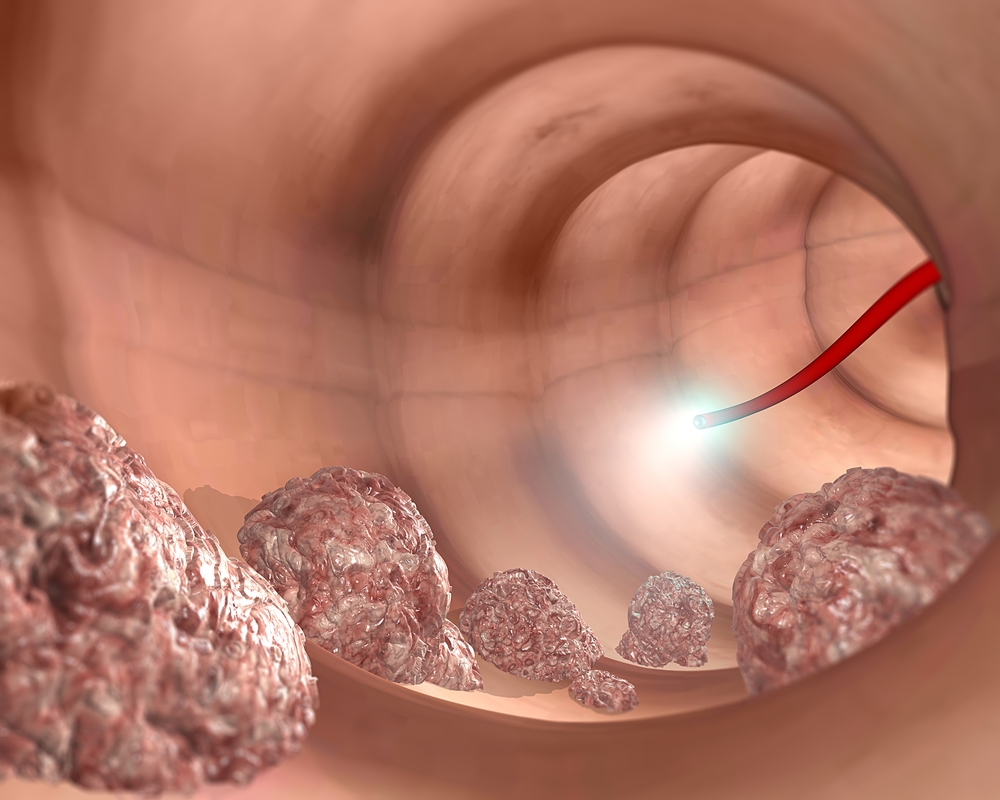

O καρκίνος του πρωκτού είναι μια ασθένεια στην οποία κακοήθη (καρκινικά) κύτταρα σχηματίζονται στους ιστούς του πρωκτού.

Το δέρμα γύρω από το εξωτερικά από τον πρωκτό ονομάζεται περιπρωκτική περιοχή. Οι όγκοι σε αυτόν τον τομέα είναι οι όγκοι του δέρματος, δεν είναι καρκίνος του πρωκτού.

Πιθανά συμπτώματα καρκίνου του πρωκτού περιλαμβάνουν την αιμορραγία από τον πρωκτό ή το ορθό ή βλάβες κοντά στον πρωκτό.

- μία βλάβη κοντά στον πρωκτό (εκδορές, έλκη, εξογκώματα κτλ.)